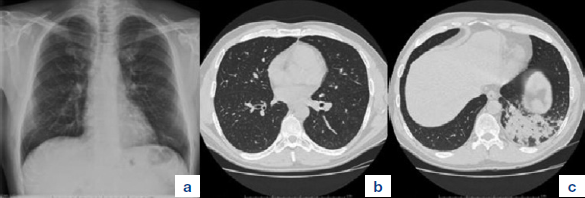

Un uomo di 49 anni, forte fumatore, bronchitico cronico, si presenta nei nostri ambulatori riferendo tosse secca; riferisce che tale sintomatologia si è presentata un mese prima quando, durante un aperitivo con amici, mentre stava ridendo, ha avuto la sensazione di avere inalato un seme di zucca. Il giorno seguente tale episodio descrive l’accaduto e la sintomatologia al suo medico curante, il quale consiglia l’esecuzione di un Rx torace: l’indagine mostra la presenza di uno sfumato addensamento basale sinistro (Figura 1a).

Giunge alla nostra attenzione una settimana dopo l’esecuzione dell’Rx torace. L’esame obiettivo rileva la presenza di rantoli crepitanti alla base sinistra e broncospasmo diffuso, maggiore a sinistra. Agli esami ematochimici lieve screzio degli indici di flogosi (PCR 3 mg/dl).

Consigliamo quindi l’esecuzione di TC torace con urgenza che mostra la presenza di ispessimento delle pareti del bronco lobare inferiore sinistro (Figura 1b) con addensamento parenchimale compatto nel lobo inferiore omolaterale (Figura 1c).

Figura 1.a. Rx torace iniziale che mostra la presenza di sfumato addensamento parenchimale basale sinistro. La successiva TC torace mostra la presenza di ispessimento delle pareti del bronco lobare inferiore sinistro (b) e di adddensamento parenchimale compatto del relativo lobo (c).